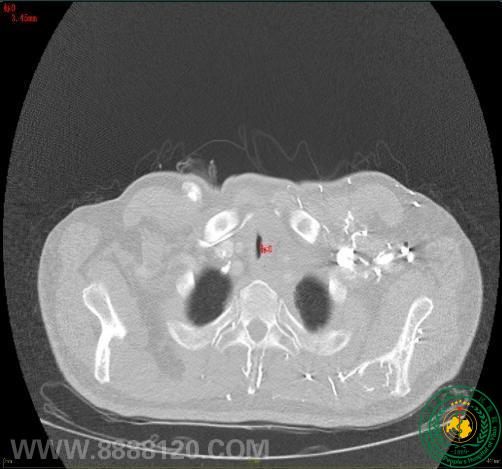

多学科合作的ECMO辅助全麻行气道支架置入术:成功抢救重度气管狭窄食道癌患者

多学科合作的ECMO辅助全麻行气道支架置入术:成功抢救重度气管狭窄食道癌患者58385